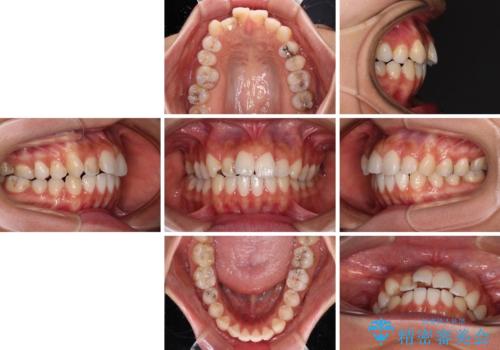

- 前歯のデコボコと口元の突出感を気にして来院された患者様です。

口元の突出感が認められ、更には左右で異なる咬合状態であったため、下顎右側は第二小臼歯を、左側は第一小臼歯を抜去することでバランスを取るような治療計画としました。

また上顎前歯は大臼歯に補綴治療が必要であったため、矯正治療後にオールセラミッククラウンによる補綴治療を行うこととしました。